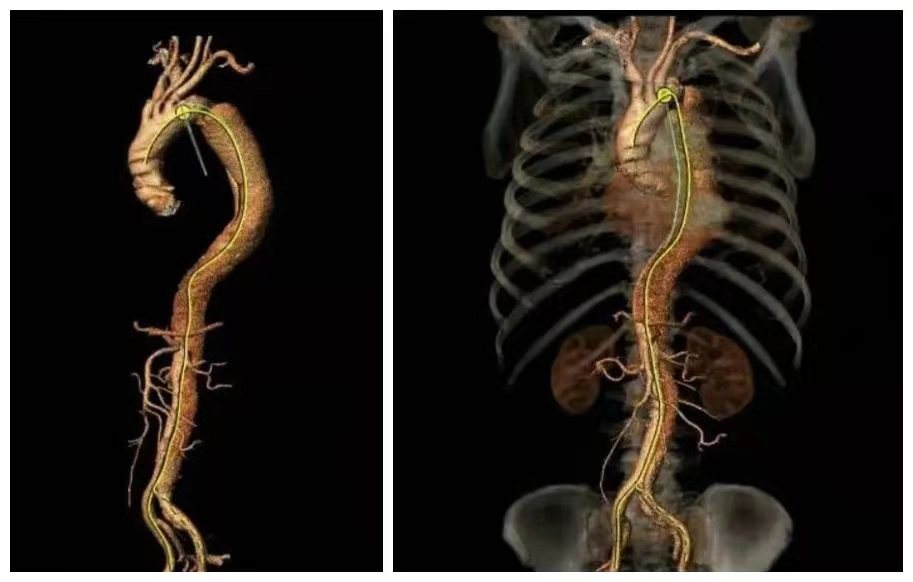

患者男性,67岁,因咳嗽、胸部不适就医,CT检查提示主动脉夹层(B型)、主动脉弓及腹主动脉硬化,局部形成钙化斑块,随以“主动脉夹层瘤”急诊收住。

时间就是生命,我院立即开辟绿色通道,以最快捷、最高效的就诊流程,积极完善术前准备,在局部麻醉下经腹股沟股动脉穿刺行“主动脉夹层腔内修复术”。西安交大一附院血管外科专家、主任医师冯骏教授亲临指导,手术顺利,破口封闭,血管真腔开通,整个手术过程历时约30分钟,患者生命体征稳定,术中、术后未诉不适;术后第二天,患者可下床活动;术后第三天,患者康复出院。